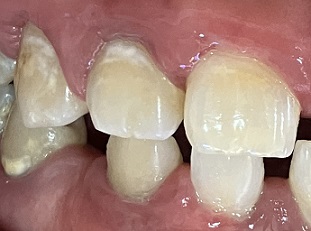

下画像1

唇側に歯石の付着 歯肉の腫れあり